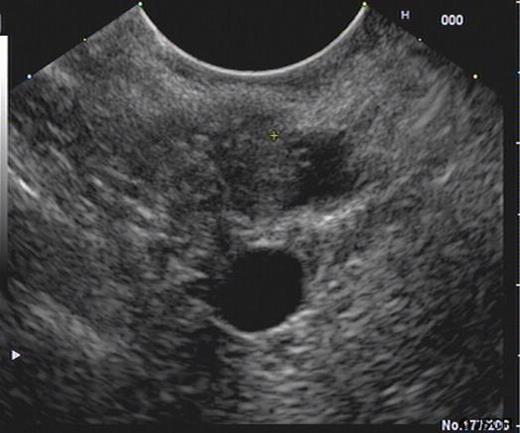

SC was a 46 yr old gentleman who was referred from his district hospital with a six month history of upper abdominal pain and weight loss. His past medical history included a prolapsed lumbar disc and he was not on any regular medications. A family history revealed that his grandfather had gastric cancer. He was a non-smoker and had a moderate alcohol intake. A Computer Tomography (CT) scan of his abdomen and pelvis revealed no significant abnormalities except for changes suspicious of duodenal diverticular disease. Prior to his consultation he had endoscopies of both his upper and lower gastro-intestinal tracts which were reported as revealing no abnormalities. An Endoscopic Retrograde Cholangio-Pancreatogram (ERCP) was precluded due to the difficulty of the duodenal diverticulum obscuring the ampulla of Vater. A subsequent Endoscopic Ultrasound Scan (EUS) revealed an 8mm soft tissue lesion in the distal common bile duct (CBD) causing dilatation of the pancreatic duct (Figure 1). Elastography showed this to be a firm mass. FNA sample were subsequently taken from the mass which revealed no malignant cells. The HPB MDT meeting felt that although the lesion could be benign, a malignant process could not be excluded thus a Whipple’s procedure was advised.

An ultrasound prior to this clinic appointment revealed a dilated Common Bile Duct (CBD) of up to 10mm, a distended thin walled gallbladder, no calculi and a normal pancreatic body. The head of the pancreas was not visualised. Laboratory tests from the GP revealed an elevated bilirubin of 150 umol/L. The CT of his abdomen and pelvis confirmed a dilated CBD and some areas of focal calcification on the head of the pancreas (Figure 3). The EUS demonstrated a thickened distal CBD with a 1.5cm hypoechoic lesion in the pancreatic head (Figure 4). The HPB MDT meeting suspected a malignant lesion and felt that a Whipple’s procedure would offer the best chance of cure.

EUS demonstrating lesion at the pancreatic head with thickening of distal CBD